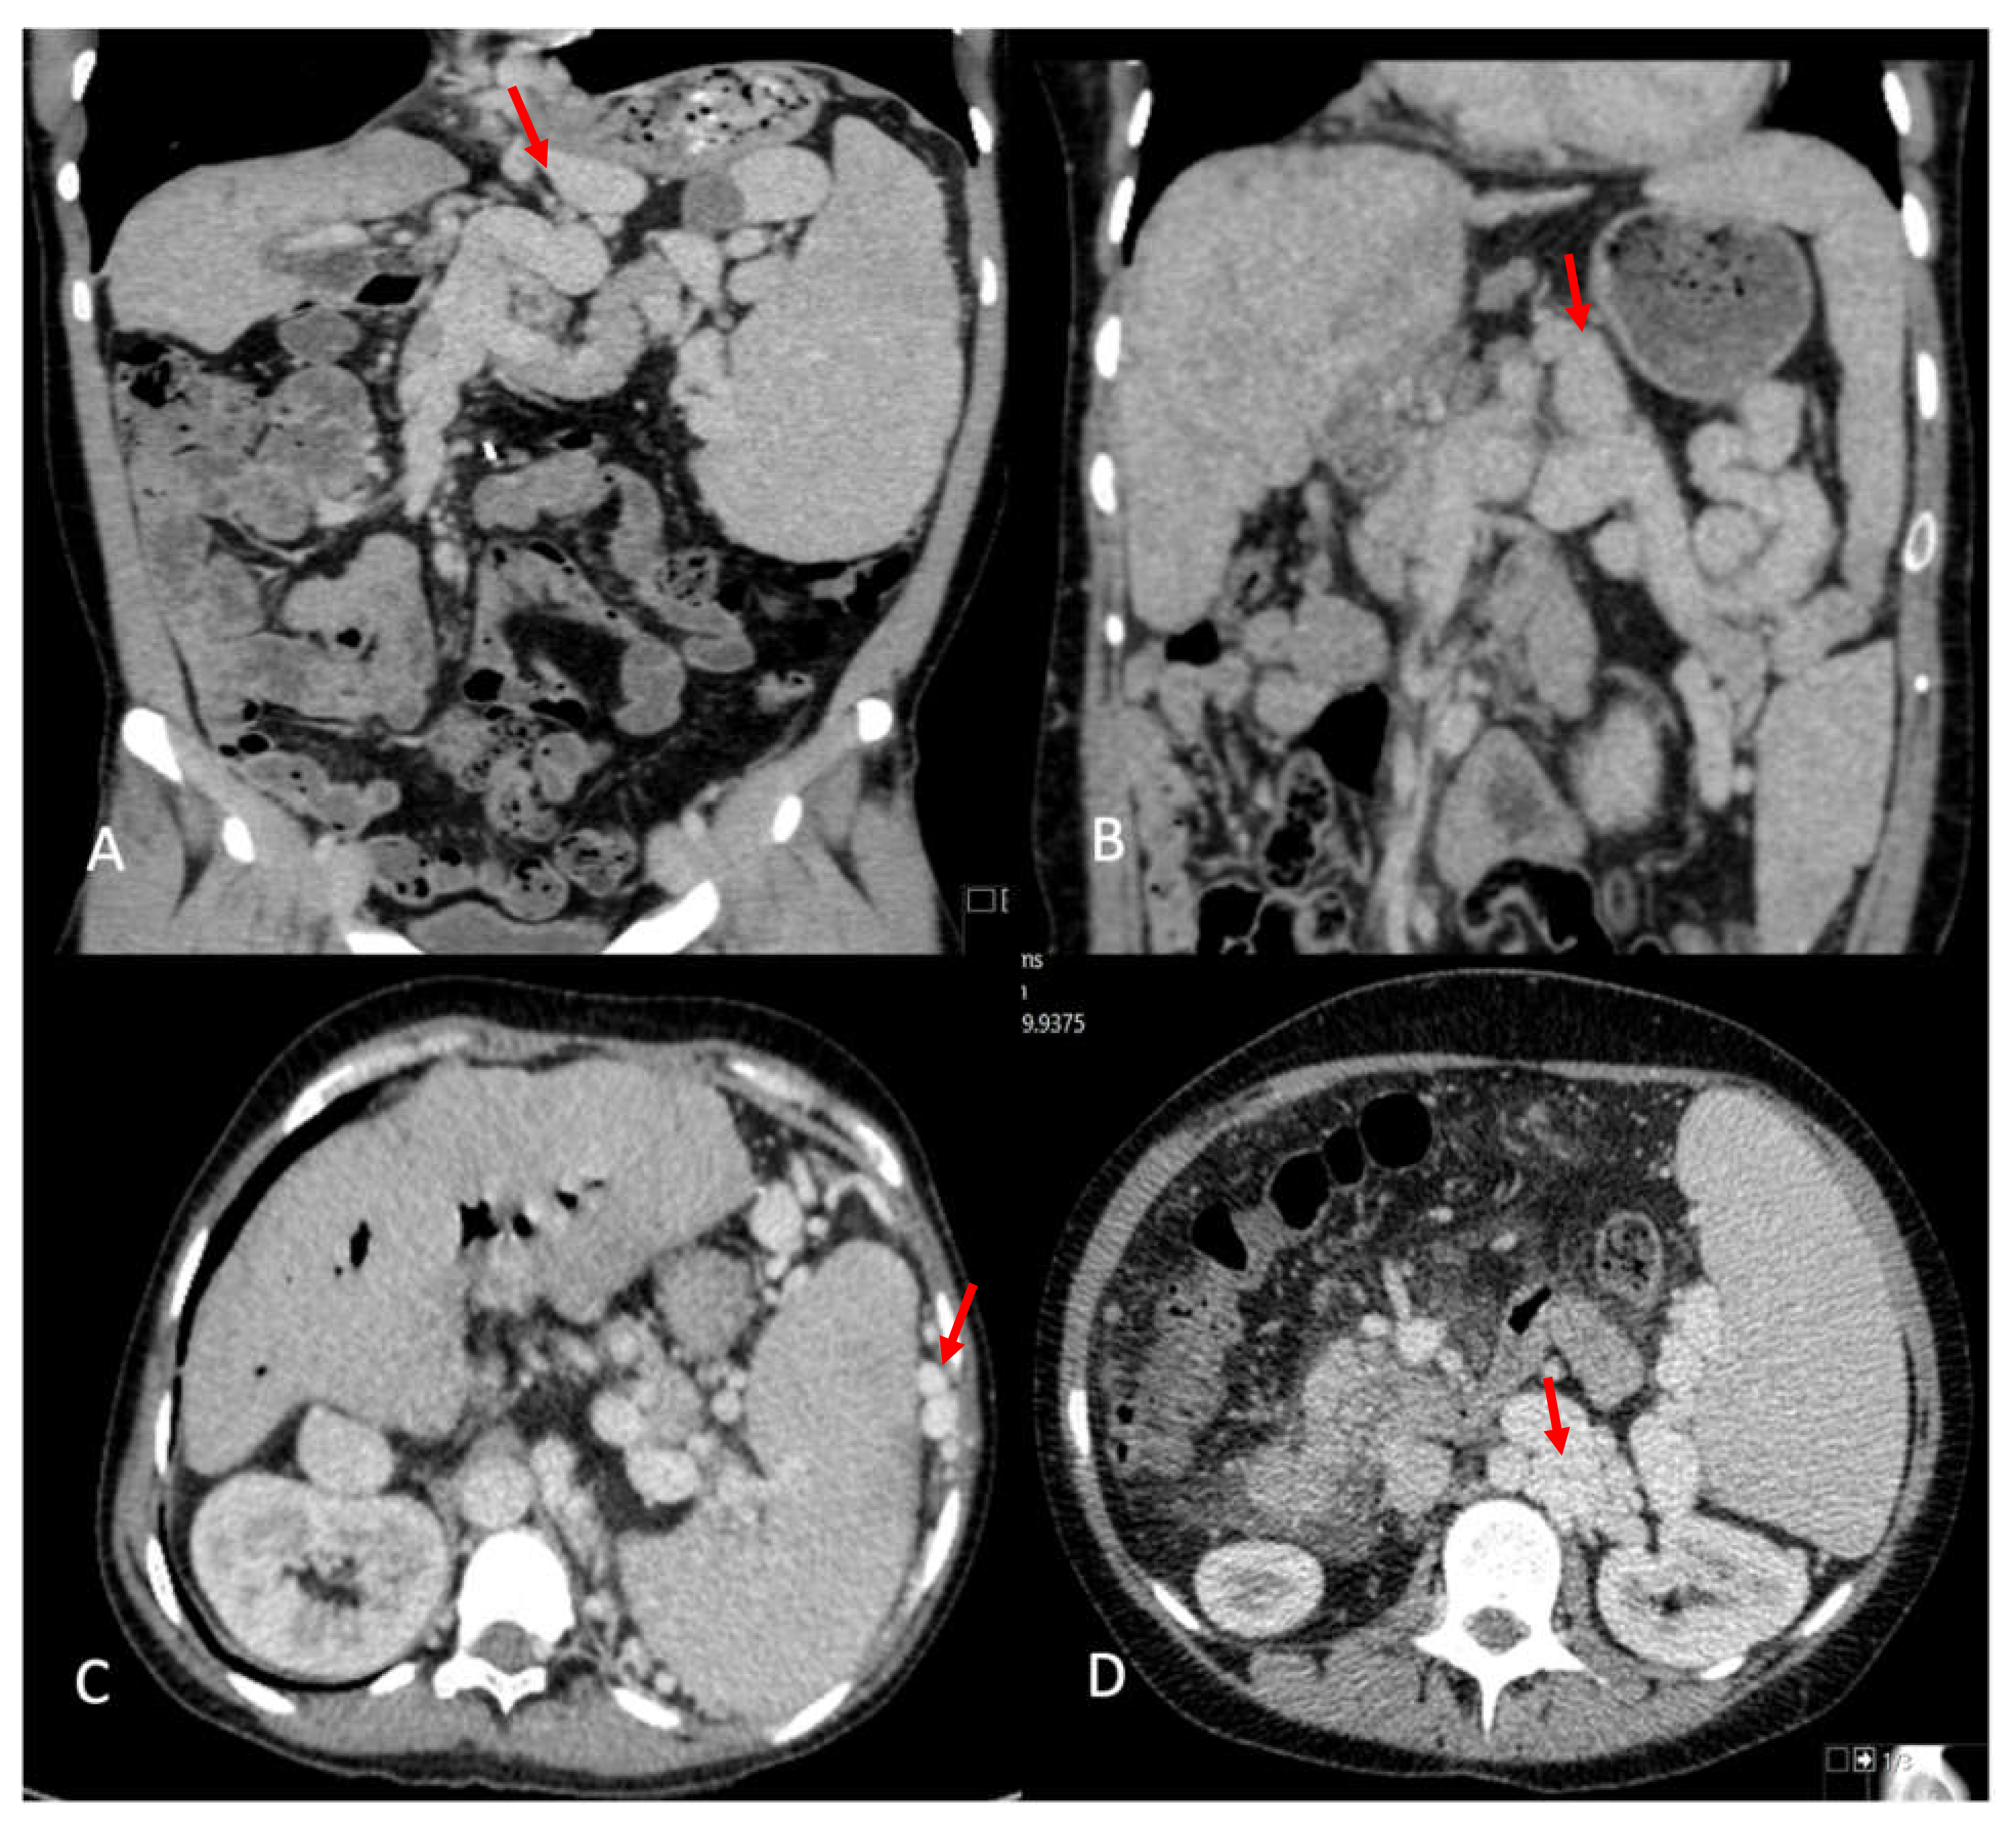

| Arterial aneurysm | |

| Splenic artery | 7 (21.2%) |

| Hepatic artery | 2 (6%) |

| Enlargement of the splenic artery | 18 (52.9%) |

| Intrabdominal variceal shunting | |

| Total number of patients | 24 (68.6%) |

| Retroperitoneal | 22 (64.7%) |

| Perisplenic | 14 (41.2%) |

| Lieno-renal | 9 (26.5%) |

| Left gastric territory | 7 (20.6%) |

| Portal vein findings on US | |

| Low velocity antegrade | 2 (6.1%) |

| Retrograde | 5 (15.2%) |

| No flow | 5 (15.2%) |